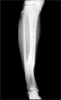

18 years old male with malunion distal tibia

Pre

Op

Xrays of limb